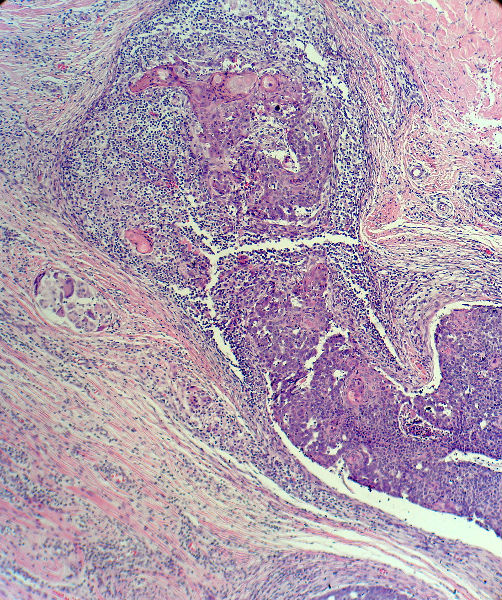

男,49岁,后枕部肿物3年,偶有破溃出血。

大体:皮肤半球形隆起,大小约2.3×2厘米,高出皮表0.8厘米,切面灰白,质地细腻。

基底细胞癌。

似乎既有腺样结构,也有角化珠形成,还有细胞团内的粉刺样坏死。

基底细胞样鳞状细胞癌。

考虑外毛根鞘肿瘤,局部癌变。

大部分区域看着象基底细胞癌,后面几张(11-14)看着象是鳞癌。综合考虑基底细胞样鳞癌。